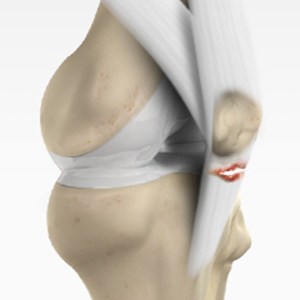

Patellar Tendinitis

Patellar tendinitis, also known as "jumper's knee", is an inflammation of the patellar tendon that connects your kneecap (patella) to your shinbone. This tendon helps in extension of the lower leg.